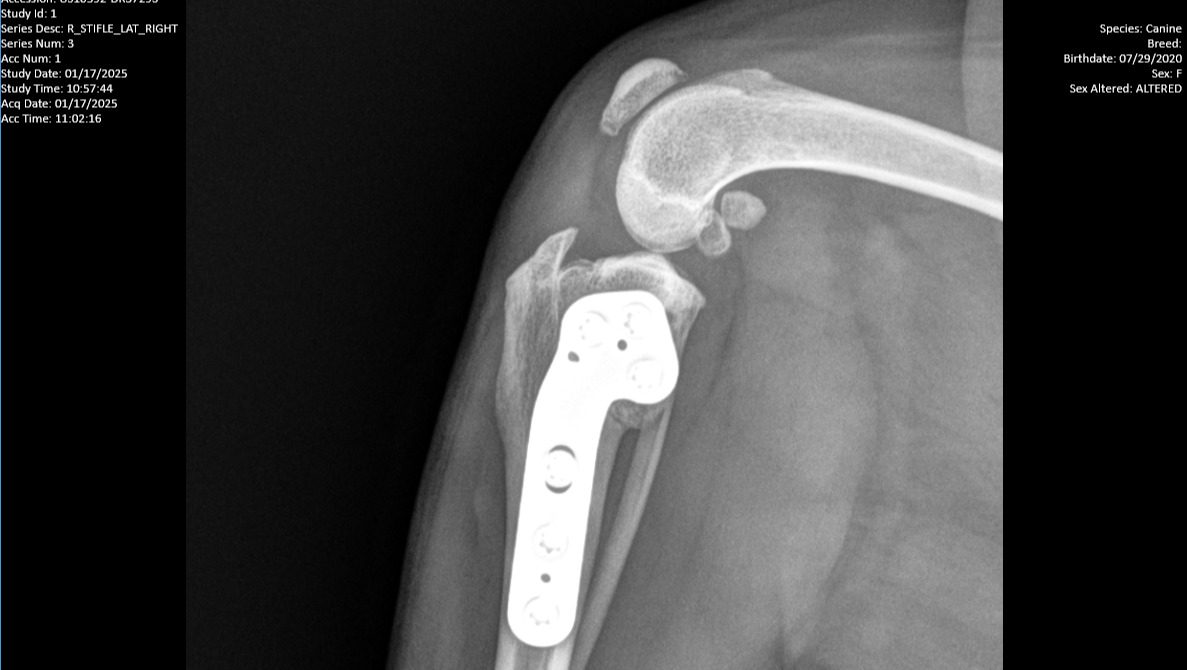

Here's 8 week X Ray's post-op of her first TPLO surgery: